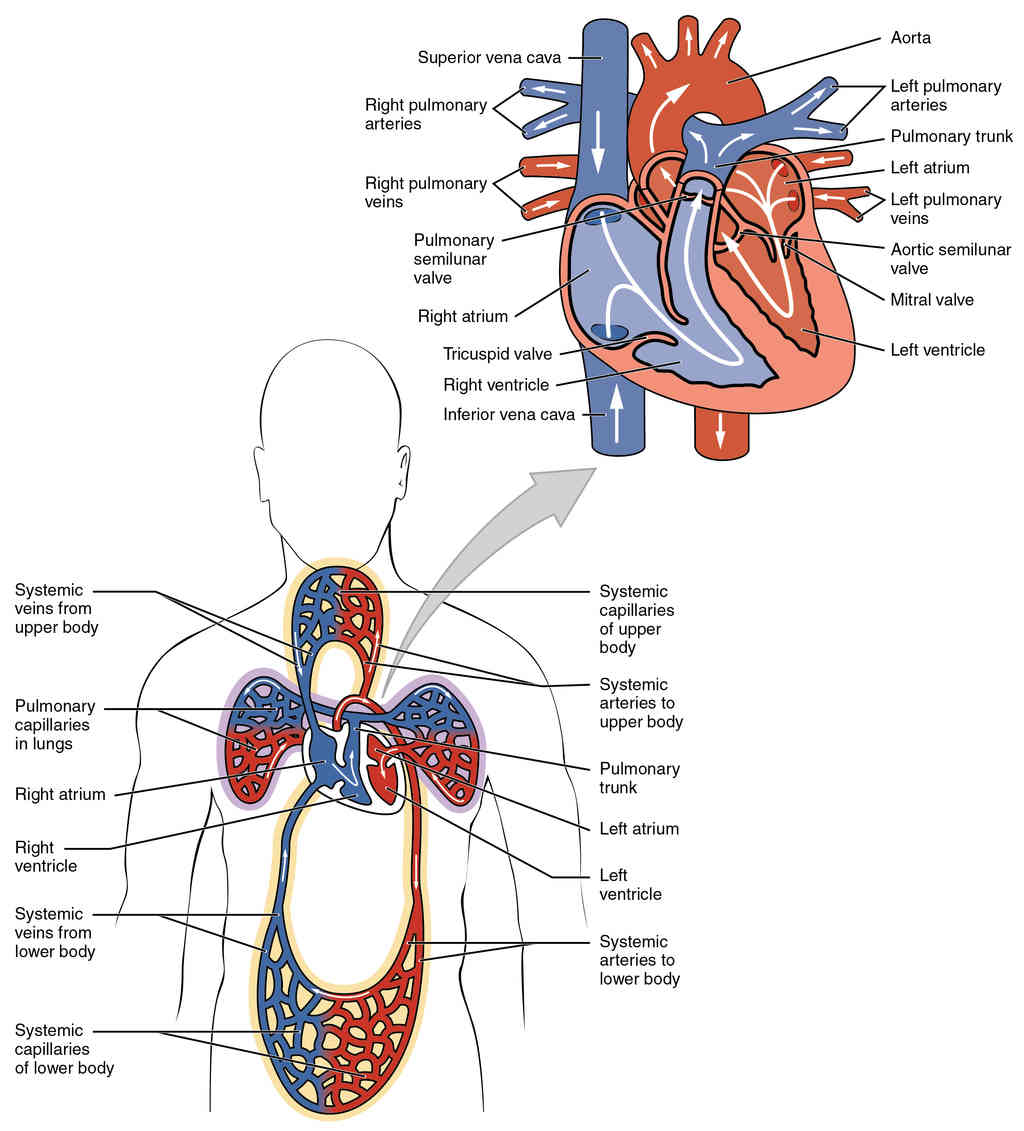

This page is under construction. For now, it is just a resource of the images found in the OpenStax Anatomy and Physiology Handbook. It wil slowly change into a revision tool. Each slide has a number. Use this to refer to the slide. When completed, it will have an unlabelled section, with labelled slides in parallel. On the unlabelled slides, write your answer and use the labelled slide to assess yourself. Keep track by also noting the number on each slide. Improvement at each attempt is important, more so than full marks on a first attempt.